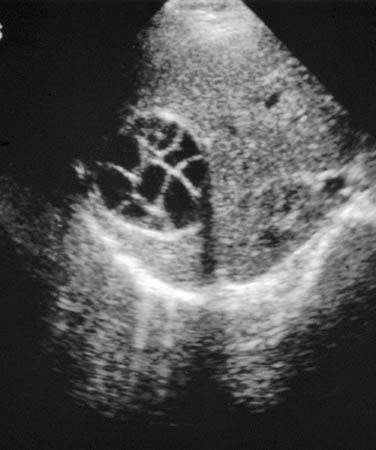

Echinococcus of liver with daughter cyst on ultrasound: multivesicular, multiseptated cysts, where daughter cyst completely fills the unilocular mother cyst; cyst produces a wheel-like structure

From the personal collections of Dr Christina Coyle and Dr Maheen Saeed; used with permission